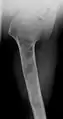

X-ray showing enchondromas localized in the humerus of a 37-year-old patient affected with Ollier disease

Enchondromas localized in the upper part of the humerus of the same patient